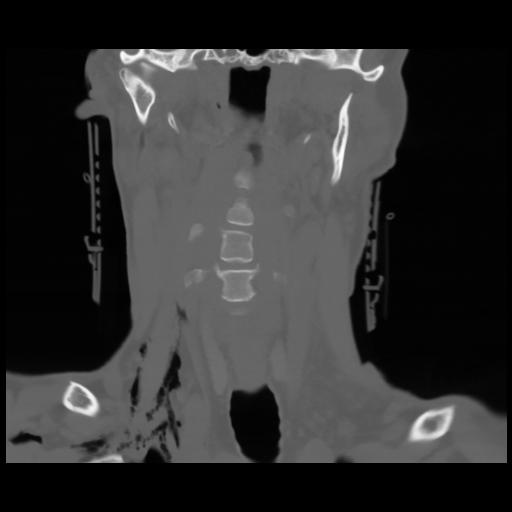

13 P.BLANDAS,,Coronal,2.000,P.BLANDAS,Coronal,